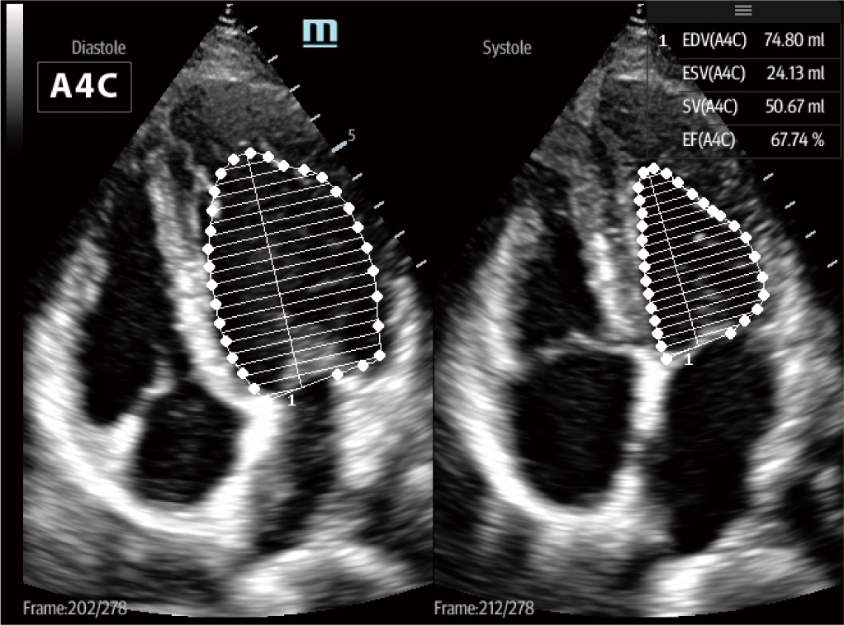

After incubation of COVID-19, the invasive of virus would cause pulmonary damage which will eventually result in respiratory failure and lead to circulation and multi-organ dysfunction. TE7 ACE equipped with professional lung preset and cardiovascular evaluation features such as Smart VTI, Smart B-line, AutoEF, TDI etc., can efficiently assist physicianto monitor cardiac profile and fluid status during clinical therapeutic procedure.